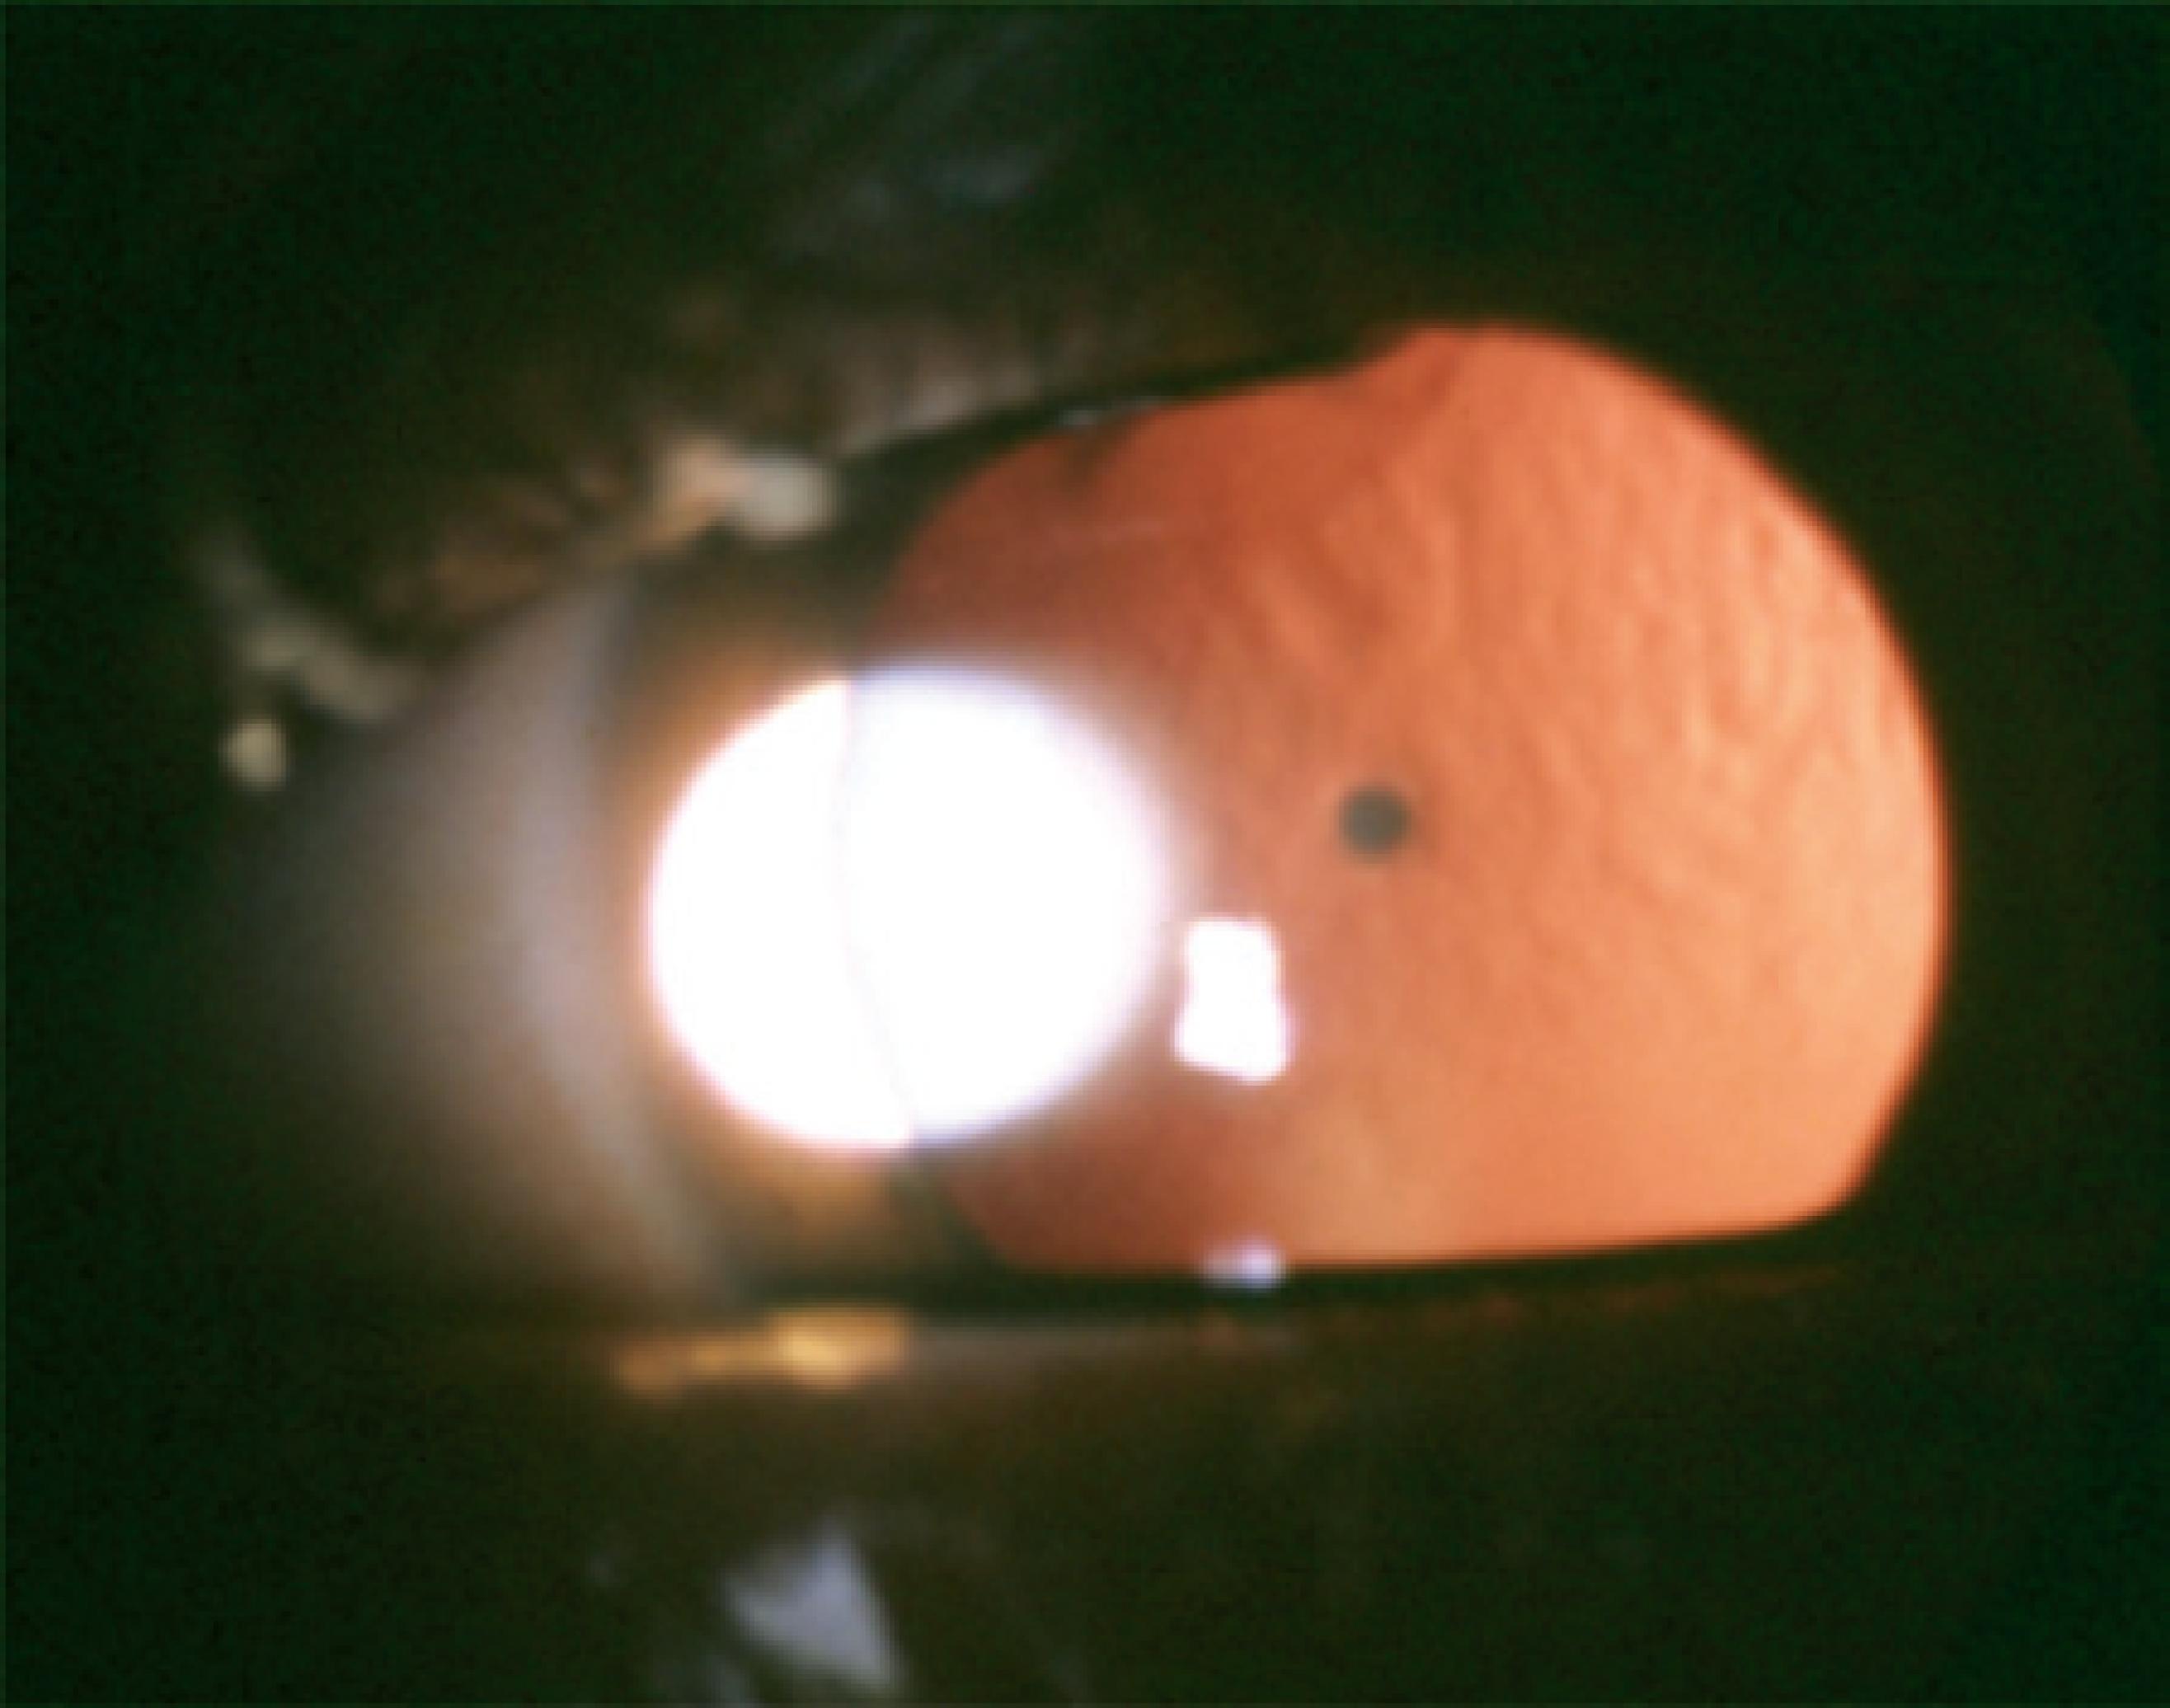

Cataract was classified according to the morphology as total (Figure 1), zonular, polar, capsular, and membranous. Zonular cataracts, which effect the fetal nucleus of the lens, were further classified as lamellar (Figure 2), pulverulent (Figure 3), nuclear (Figure 4), and sutural. According to the site of lens opacity, polar cataracts were classified as anterior, posterior, or pyramidal (Figure 5). Capsular cataracts were further classified as anterior, posterior, and lenticonus. When multiple morphological types of cataract co-exist in the same child or in the same eye, they are considered as mixed cataract.

Morphology or laterality of pediatric cataract may be indicative of its etiology. Hereditary cataracts display a variety of phenotypes, more frequently display a zonular morphology (Figure 3), and are usually bilateral. In most cases, the opacity of the lens caused by PFV are unilateral posterior subcapsular, which progress into complete opacity of the lens. We found that among the PFV patients, 52.94% had posterior subcapsular cataract (Table 4). Nuclear cataract (Figure 4) is usually detected at birth, whereas lamellar cataract (Figure 2) develops at a later stage and can be progressive. Visual prognosis may depend on the morphological type, with less favorable outcomes in cases of total cataracts(26).